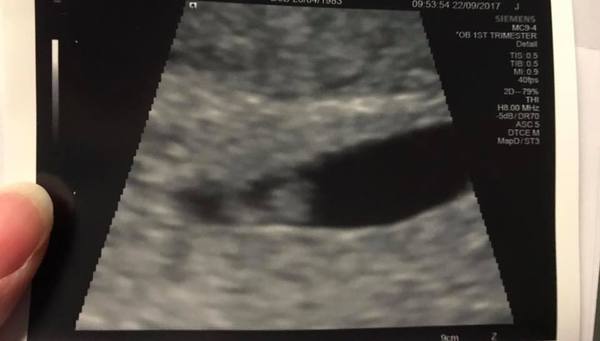

Hello everyone! Those on Facebook group may have seen this, but thought I'd update here too. So, last Friday at 5+3 I went to A&E with spotting and cramping. Saw a doc in the EPU and he examined me, filled about for ages and then concluded that my cervix was open and I was therefore having a miscarriage. He mentioned polyps as well but said as my cervix was open miscarriage was inevitable. Told me to come back the following week (today) for a scan to see if I'd lost the baby. I bled loads after the exam but it tapered off that evening and I had nothing after that. Had an awful week of worrying and went for my scan this morning. There was a little baby with a lovely heartbeat measuring 6+1! A couple of cysts on my ovaries but nothing concerning and my cervix is well and truly closed. She said either it was open for some reason and has since contracted, or it was never open in the first place. Just goes to show you, the doctors can sometimes be wrong!!

Meet Baby B number 3 :)